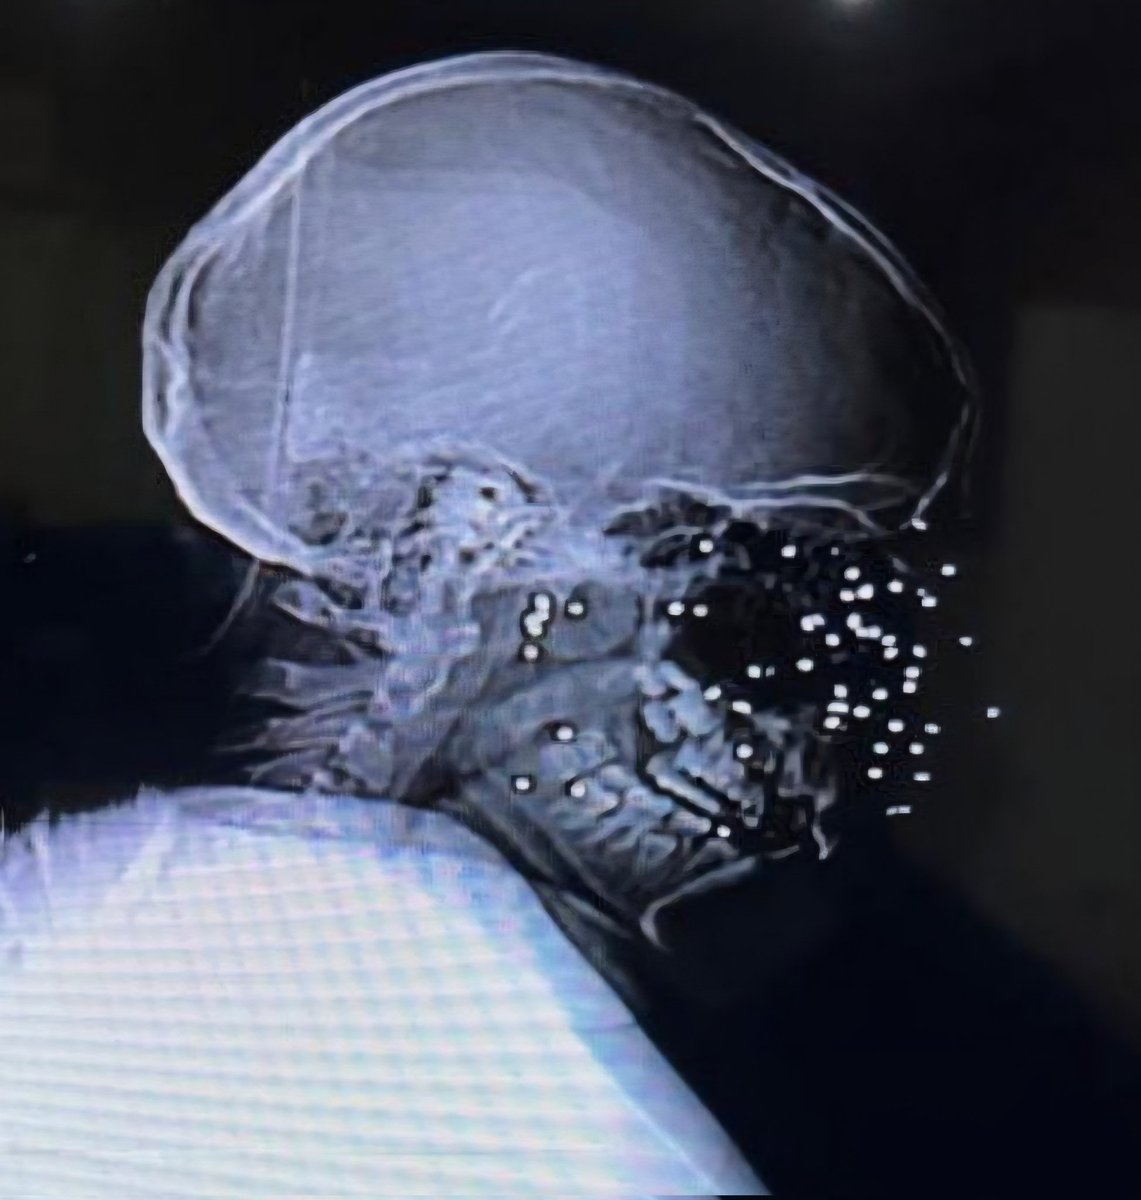

Another scout image from a CT angiogram of the head and neck of an Iranian protester shot in the face with a shotgun loaded with birdshot. Iranian physicians are reporting hundreds of patients with shotgun wounds to the face, most with severe eye injuries. The Ayatollah is

@DrJacobsRad

These are scout images from a CT scan of a young Iranian protester. There are 47 pellets in her face. This is typical of BB shot, meant to take down large birds. She will never see again. I am outraged by the world's indifference to the Ayatollah's brutality. #IranMassacre